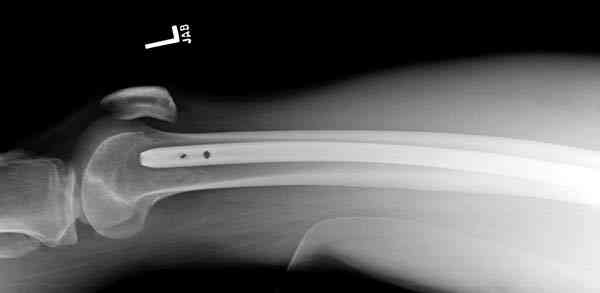

В нашем случае 21 летний боец уличного фронта, фиксацию провели на следующий день, зафиксирован интрамедуллярным штифтом. Не стали делать первичную хирургическую обработку точечной раны, зафиксирован как есть. Клинические снимки: